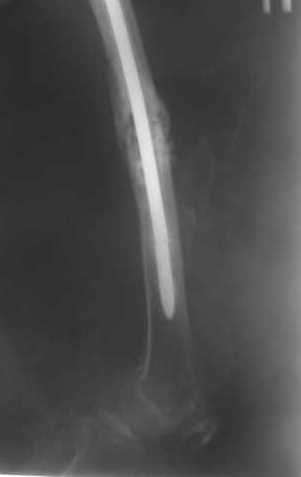

В приложении как раз видна эволюция использововшихся у нас большеберцовых гвоздей. Первый - дизайн как у UTN, второй - разнесены 45 градусные отверстия (зачем их вообще изначально так нелепо на одном уровне сделалм???), третий - убрано сиавшее лишним статическое отверстие, Herzog's bend перемещен более проксимально.

В приложении пример, дистальный отломок пружинил кзади. Два винта потому, что первый оказался чуть кпереди и не упирался в гвоздь.